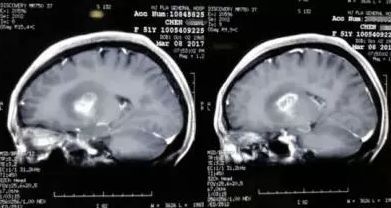

腦瘤不做手術,保守控制是的方法。以腦膠質瘤為多見,約占50%以上,經手術化療后,5年生存率不足20%,大部分患者術后1~2年內復發,轉移腦瘤多半手術后半年內死亡,1年以上存活者不足15%。

腦瘤不做手術,保守控制是的方法。以腦膠質瘤為多見,約占50%以上,經手術及放、化療后,5年生存率不足20%,大部分患者術后1~2年內復發,轉移腦瘤多半手術后半年內死亡,1年以上存活者不足15%。

我身邊有好多個腦瘤的,都說是控制就可以,一做手術活不了多久,有一個朋友的媽媽沒下手術臺。錢伯文認為腦瘤以痰濁上擾、清竅受蒙、氣血郁結為主證。腦膠質瘤3級,手術后還能活多久?臨床數據上給出的生存區間是1-10年,具體你能活多久,參考2個維度:一個是膠質瘤是不是長在功能區;第二就是調養免疫力等方面是否跟上了。

腦瘤是目前發病率高且較難治愈的疾病。關于腦瘤的治療,專家們提出各自的特色觀點。至少我身邊的幾位都是這樣,還不如不做手術多活幾個月。劉嘉湘教授根據腦瘤氣虛血瘀的病機特點,強調重用生黃芪,以扶正托毒。

袁世民將腦瘤的病機概括為陽虛寒邪內著,氣血阻滯以及陽氣虧損,寒凝清竅,氣血阻滯。筆者認為腦瘤治療關鍵在于補腎化瘀,益氣通絡,軟堅散結。關于腦瘤的病因,多數學者一致認為主要由于內有脾胃陽氣虛弱或肝腎陰虛,外有寒、毒邪入侵,以致痰濕、瘀毒結于髓海而成。